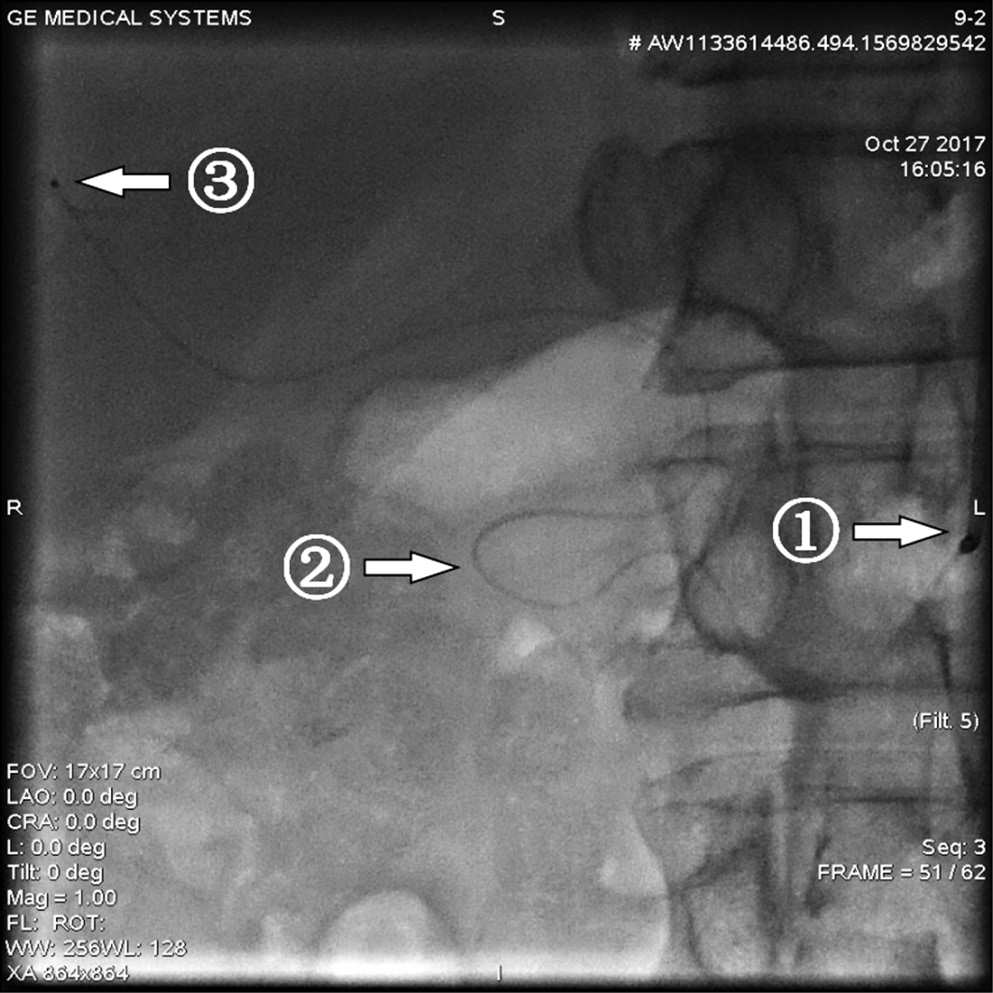

Типичная артериальная анатомия печени была отмечена у 26 (86,7%) исследуемых больных с вторичным неоперабельным метастатическим поражением печени, однако у одного пациента с типичным вариантом кровоснабжения был выявлен критический стеноз чревного ствола, еще у одного — окклюзия чревного ствола (рис. 1, 2). Таким образом, только 24 (80%) обследованных пациента имели типичный неосложненный вариант кровоснабжения печени. Другие (атипичные) варианты кровоснабжения печени наблюдались в 4 (13,3%) случаях. Следует подчеркнуть, что особенности анатомического строения сосудов печени не повлияли на результативность и завершенность процедуры ХЭПА благодаря возможности использования микрокатетерной техники для суперселективного введения микросфер (см. рис. 1, 2).

Рис. 1. Вариант кровоснабжения печени при окклюзии чревного ствола

Примечание. 1 — чревный ствол, 2 — верхняя брыжеечная артерия, 3 — коллатеральное заполнение бассейна чревного ствола из верхней брыжеечной артерии через a. pancreatiсoduodenalisinferior и ретроградно через а. pancreatiсoduodenalissuperior и a. gastroduodenalis.